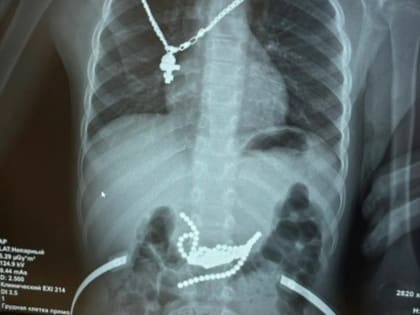

Хирурги Ростова спасли ребенка, проглотившего 50 магнитных шариков

Сложная операция прошла успешно, и мальчик сейчас в безопасности.